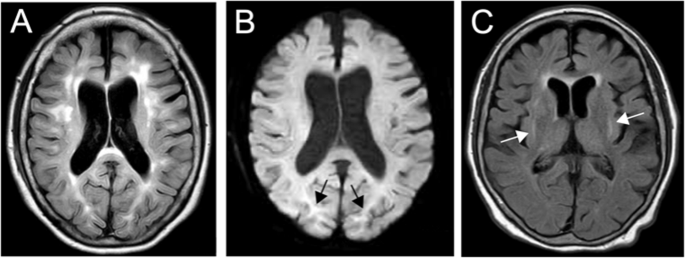

At 58 years of age, the patient noticed shaking in her hands and consulted a neurologist. During the neurological examination, she exhibited postural and kinetic tremors in her upper limbs. By age 68, she struggled with tasks such as opening or closing a water tap, operating a TV remote control/smartphone, and brushing her teeth. Additionally, she exhibited rigidity in all her limbs, leading to her admission to the neurological department. The patient’s tremors and rigidity were mild and did not significantly impair movement. However, she was unable to explain how to use necessities of daily living and could not use them correctly. Tests revealed low ceruloplasmin (8.8 mg/dL; reference range, 30–58 mg/dL) and copper (21 µg/dL; reference range, 70–140 µg/dL) blood concentrations and high urine copper excretion (2985 µg/day; reference range, 15–60 µg/day; 2000 mL urine). An ophthalmologist observed bilateral Kayser-Fleischer rings, and an MRI of the brain showed hyperintensity in the white matter, which is atypical in WD, and in the basal ganglia (Fig. 1A–C). Based on these findings, the patient was diagnosed with WD. While no family history of WD or other neurological or psychiatric disorders was reported, the patient’s son died at age 30 due to DCM, although medical details are unknown. Symptoms of WD and DCM developed earlier than the relatively late onset of neuropsychiatric symptoms, and the family history of DCM in the patient’s son prompted us to perform whole-genome sequencing (WGS) to diagnose the patient (Fig. 2A).

A FLAIR image showing periventricular hyperintensity and deep and subcortical white matter hyperintensity (axial; 1.5 T; TR, 8000 ms; TE, 100 ms). B DWI showing high-intensity signals (arrows) in the region of the corticomedullary junction in the bilateral occipital lobes (axial; 1.5 T; TR, 3732 ms; TE, 89 ms). C FLAIR image showing basal ganglia hyperintensity (axial; 1.5 T; TR, 8000 ms; TE, 100 ms).